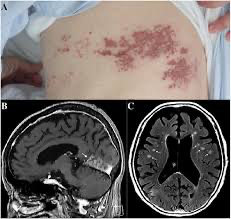

典型的には、帯状疱疹(特に眼部)の後に数週-数ヶ月かけて頭痛や脳梗塞が出てくるという病歴になります。ただここで注意すべきは、1/3の症例では先行する皮疹がないと報告されており、皮疹がなくても否定できないという点になります。そのため病歴だけでは診断できない症例もあり、その場合は他の所見から疑う必要があります。

・典型的な画像所見

前述の通り、本病態は大-小動脈が段階的/多発性に障害されるという特徴があります。そのため病変は皮髄境界に好発し、多発・両側性で時間差で増加してくるような経過をとります。MRAでは分節状狭窄や後拡張を認めることがあります。素人目には、若年者や血管リスクが高くない患者なのに、MRAで血管ボロボロという感じに見えます。

・VZV vasculopathyは、帯状疱疹罹患し数週間後に脳梗塞などの神経障害を生じる病態

・皮疹の病歴は1/3の症例では認めず、皮髄境界の多発梗塞や血管狭窄などの画像所見が重要